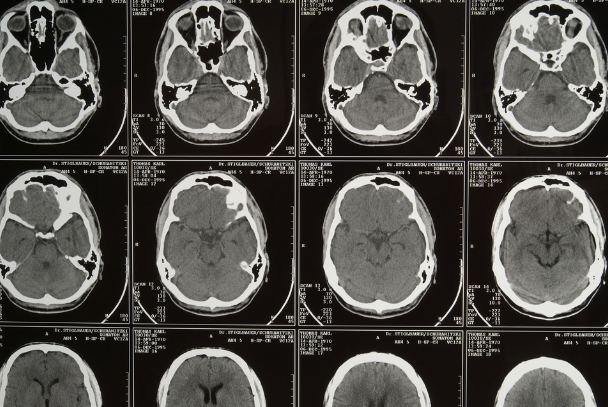

Think of the brain like an electrical grid in a busy city. Over decades, storms (stroke), heat waves (chronic inflammation), faulty wires (neurodegeneration), or aging infrastructure (frailty, multimorbidity) can strain the system. Eventually, one small surge can tip the balance.

That’s what LOE often looks like. The cause isn’t a single point—it’s accumulated life experience embedded in brain tissue.